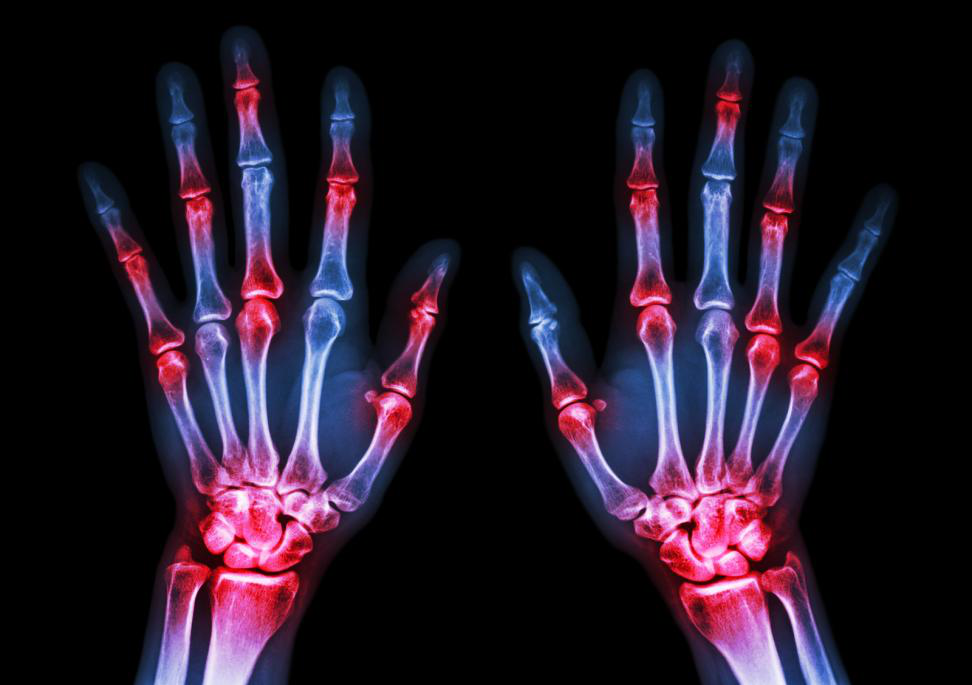

Those who have rheumatoid arthritis feel ardently need the services of a good rheumatologist in Albany. Getting a timely diagnosis and the right treatment can give a patient better access to an enhanced quality of life. In the past few years, there have been advancements in the field of rheumatoid arthritis treatment with the availability of super-specific medications for targeted action on the diseased tissues.

The right level of patient care is necessary for arthritis, and doctors also need to follow a holistic approach to the treatment of arthritis while involving the functional aspects of therapy. Including treatments like physiotherapy and other things, patients can experience tremendous improvement.